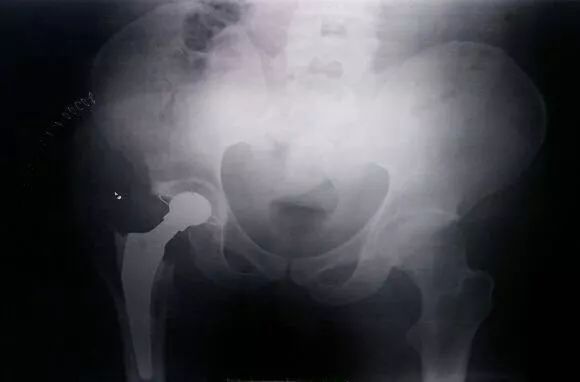

经过一番交流后我才知道,原来他叫Rock,今年22岁,是巴巴多斯人。4年前因车祸导致右侧髋臼骨折合并髋关节脱位,在当地医院进行了手术治疗,可是手术失败,术后很快再次出现髋关节脱位。

仔细研究后,我不由自主替他捏了一把汗。由于第一次手术失败后仍长期持续负重活动导致他的病情日益严重,右侧的髋关节已经遭到严重破坏,右侧髋关节的高位脱位造成右腿比左腿短缩了近8厘米。

好不容易满足了手术基本条件,等到了手术日那天,却因血源紧张拿不到血而不得不推迟一周手术,终于再经过一周的等待拿到充足的血后,顺利完成了这例“右侧髋臼植骨重建+全髋关节置换术”。

该手术是乔治敦医院首次开展的疑难骨科手术,术后第二天,Rock便已经拄拐下床行走,术后两周来门诊复诊时已经可以不用拐杖正常行走,看到他修长的身材加上英俊的面容,活脱是一个重新站起来的“男模”,我也为自己成功地修复了这件“艺术品”又增添了一分成就感。